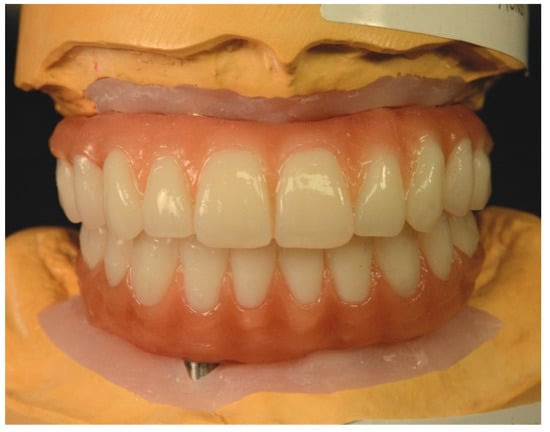

Full-Mouth Rehabilitation of a Patient with Sjogren’s Syndrome with Maxillary Titanium-Zirconia and Mandibular Monolithic Zirconia Implant Prostheses Fabricated with CAD/CAM Technology: A Clinical Report

2. Materials and Methods

3. Results